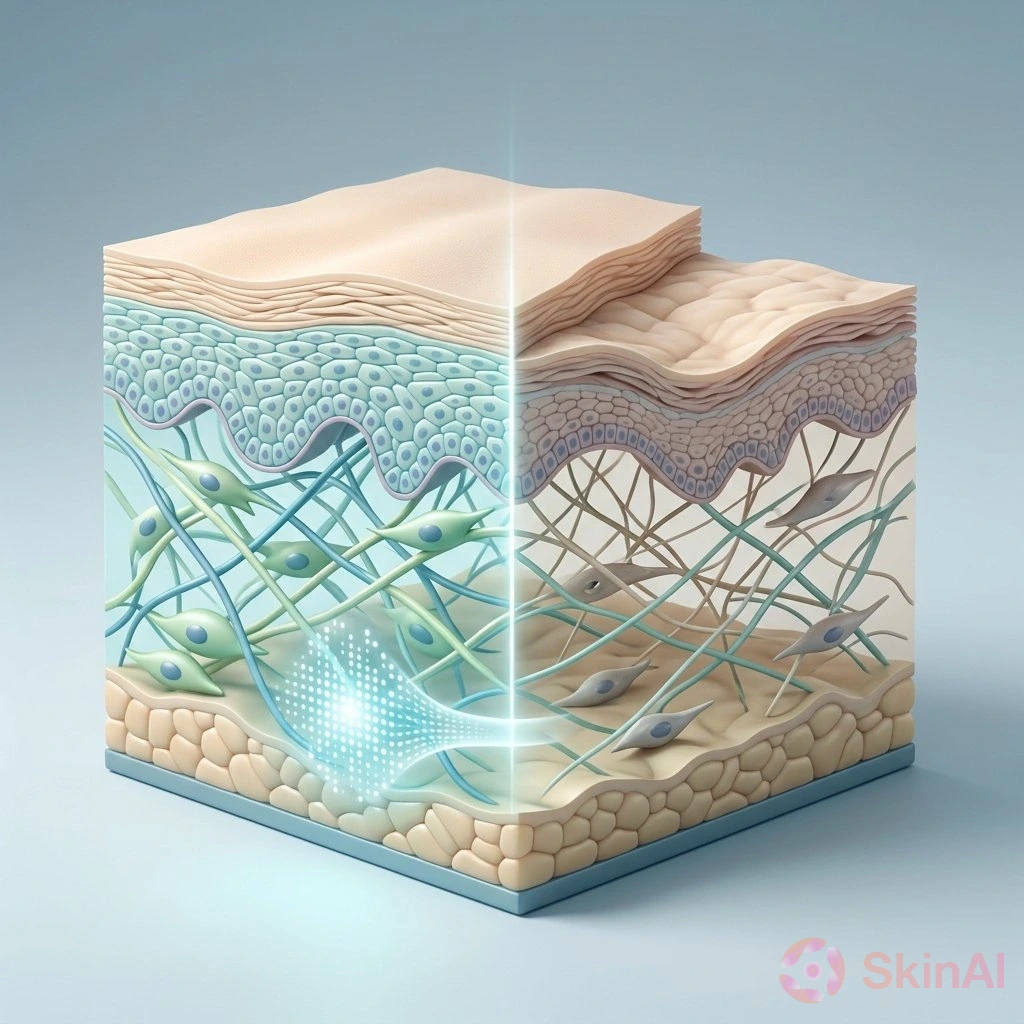

How Digital Twin Technology Is Revolutionizing Skin Treatment Choices

Discover how digital twin technology is transforming skin treatment by enabling precise, personalized care without trial and error.